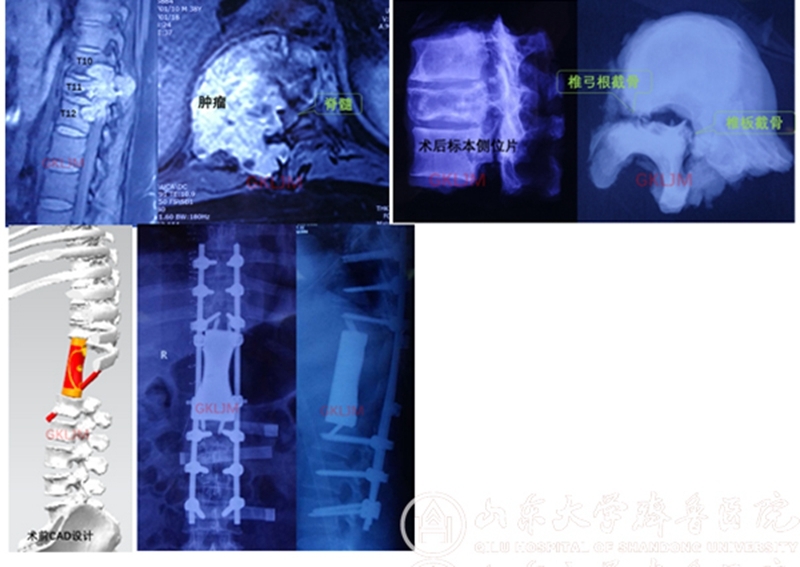

该患者因“双下肢疼痛、麻木1个月,无力10余天”来齐鲁医院就诊,之前曾在当地医院行穿刺活检,病理报告为低度恶性脊索瘤,因当地医院无能力切除肿瘤,患者慕名找到齐鲁医院骨肿瘤科李建民主任。当时患者已无法站立,处于截瘫的边缘,检查发现肿瘤累及第10-12三个胸椎,右侧椎旁形成软组织包块并侵犯膈肌,肿瘤侵入椎管压迫脊髓造成截瘫。

患者影像学检查

1月30日,经过充分术前准备后手术开始了,先在病椎上下各置入6枚椎弓根螺钉,切断并部分切除双侧6根肋骨,将脊椎一侧椎弓根打断,另一侧则经椎板截骨以减少肿瘤污染,整块切除后方附件,将三节段椎体绕过脊髓从右侧取出。李建民团队历时14个小时,克服了出血凶猛过万毫升的困难,顺利完成第10-12胸椎三节段切除,3D打印假体精准重建。术后患者恢复顺利,下肢感觉肌力逐渐好转。